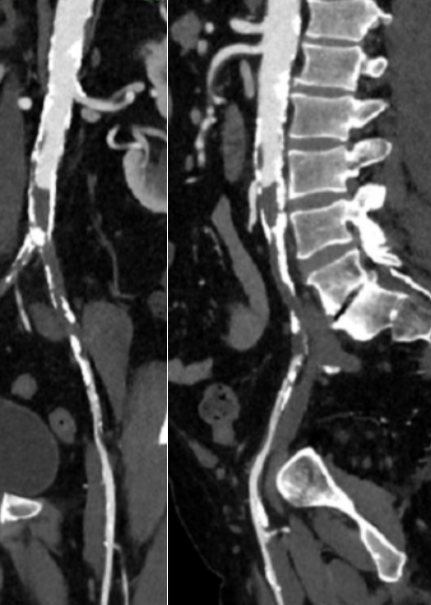

The patient was a 50 something year old man who I took care of in 2016 before I left for Abu Dhabi. He had a background of hypertension, hypercholesterolemia, and IDDM with chronic immunosuppression for rheumatoid arthritis. For several weeks he had rest pain in his feet and impending gangrene of his left great toe. More worrisome was the development of punched out ulcers on his groin crease resulting in weeping wounds after a bout of cellulitis. He had no palpable femoral pulses. Pulse volume recordings showed flat lines from the thigh to the feet.

CTA of the abdomen and pelvis with runoff showed aortic occlusion due to heavily calcified plaque with reconstitution of the external iliac arteries via the internal iliac arteries. The common femoral arteries were only mildly diseased and there was patent runoff.

Centerline up right femoral into aorta shows occluded aorto-iliac segment and diseased external iliac artery.

Centerline up left femoral into aorta shows mirror image of disease on left side

In the five years since the operation, he has needed an SMA stent and has devloped worsening CKD and autoimmune diseases. But one of the gratifying things is he healed his wounds on this groins and thighs and the left hallux, and pain has never recurred. He had a contrast CT at the 5 year point (figure) showing a widely patent graft, and he sought me out when he heard that I was back in Cleveland.